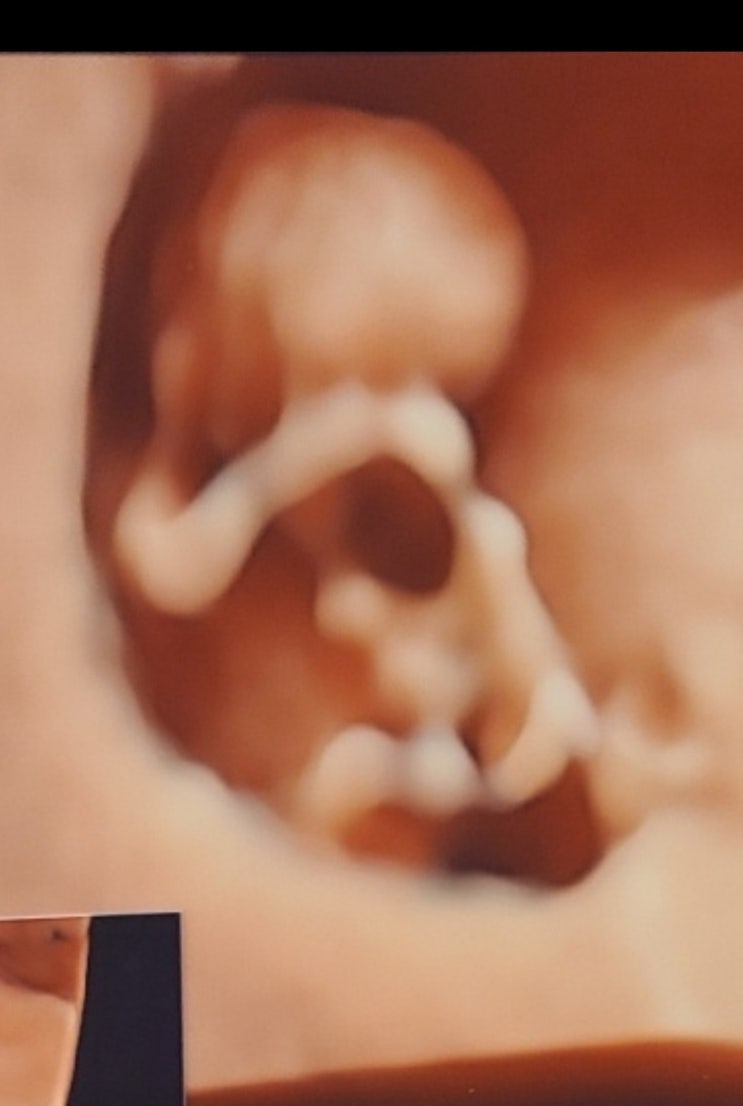

18주3일임산부 코로나 확진 후 첫 산부인과 방문

22.03.02 코로나 확진 후 이제 거의 증상이 없어져서 2주 3일만에 처음 병원을 갔다. 2주까지는 거의 나았...

15주3일차

2월10일 목요일 발렌타인데이를 위해 초코빼빼로를 만든다고 조금 서있었더니 갑자기 밑에서 물 같은게 왈...

13주차

이제 병원예약은 2월16일이라서 당분간 초음파를 못보니...아이가 잘 있는지 확인할 길이 없으니 궁금해서 ...

11~12주

11주3일차 22.01.12 1차기형아검사를 받으러갔다. 맘까페서 보니 보통 12주차에 많이 받는거 같았는데 11주...